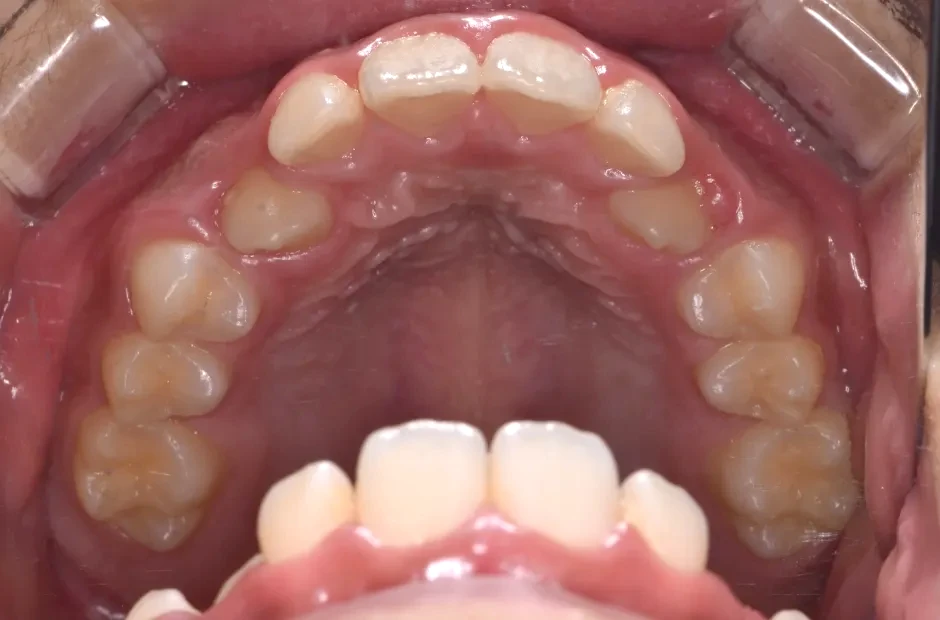

前歯部反対咬合

| 診断名・主訴 | 前歯部反対咬合 |

|---|---|

| 年齢・性別 | 14歳・男性 |

| 治療期間・回数 | 1年2か月 |

| 治療に用いた主な装置 | ブラケット矯正 |

| 抜歯部位 | なし |

| 治療費 | 60万円(税抜) |

| リスク・副作用 | 装置による違和感・疼痛・歯肉退縮・歯根吸収・虫歯のリスクなど |

治療前

治療後